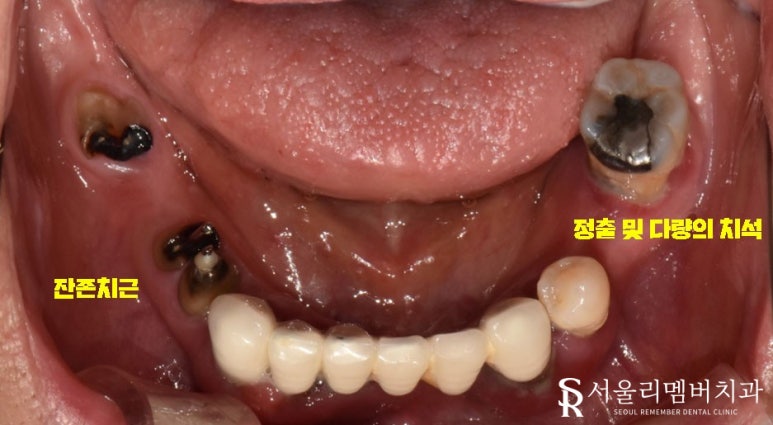

네, 한눈에 봐도 여기저기 망가진 치아들이 관찰되는데요.

이수역 치과 에서 좀 더 자세히 살펴볼까요?

정출

치경부 드러남

빠져버린 치아

다량의 치석

치주 질환

잔존 치근

정밀 검진을 하지 않았는데도 불구하고 위와 같은 문제들이 발견되었습니다.

아무래도 간단하게 해결되진 않을 것 같은데요.

구강을 뒤집어엎는 대공사가 필요해 보입니다.